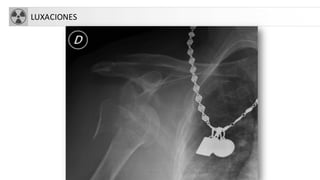

• Luxación: Pérdida completa de continuidad entre2 extremos óseos.

Las más frecuentes

– Gleno-humeral

– Codo

– Tobillo

– Articulaciones interfalángicas.

LUXACIONES

LUXACIÓN HOMBRO

• La articulación glenohumeral posee el mayor grado de movilidad del

aparato locomotor

• Mecanismo: abducción forzada acompañada de una rotación

externa del brazo

• En ancianos, suele estar acompañada por la avulsión del troquíter

• Es la articulación que se luxa con más frecuencia

• Tipos

– Luxación anterior: más frecuente. Dolor, impotencia funcional,

parestesias. “Hombro en charretera”. Se asocia a Fx troquíter

– Luxación posterior: más frecuente en ancianos. Muy dolorosa

– Luxación erecta/inferior: “saludo hitleriano”

– Luxación superior: muy rara. Requiere fractura asociada